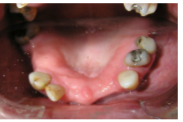

Extraction of the UR1

Single Implant placement UL1 for cantilever bridge

• Immediate implant placement in the UR1 extraction area would be highly risky due to previous infection and skill required to place implant in the correct restorative position

• We took into account the age of the patient and failure in the UL1 site may allow the UR1 site to be used in the future